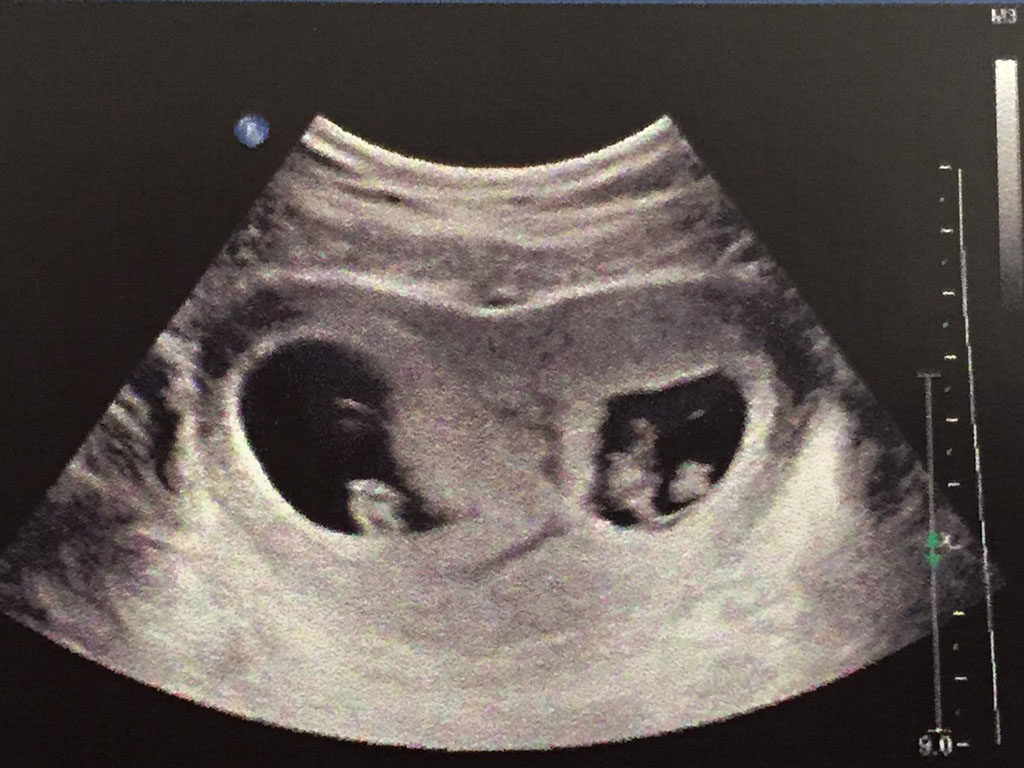

Shaniece was had just finished her second trimester when she visited the doctor for her 10-week scan. She twiddled her thumbs above her bump as she lay on the table. When the doctor returned with paperwork, he was silent.